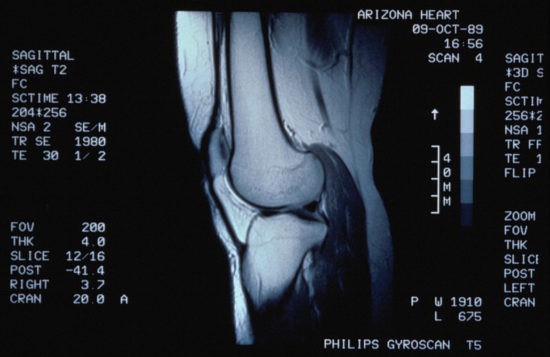

Что показывает МРТ-снимок коленного сустава

Снимок МРТ коленного сустава отображает все элементы Articulatio genus:

- костная ткань. Сканирование показывает любые дегенеративные и воспалительные изменения, произошедшие в коленной чашечке и суставной головке;

- хрящи. Снимок помогает выявить степень износа хрящевой ткани и возможные повреждения;

- связки и сухожилия. Магнитно-резонансная томография помогает определить растяжения, разрывы и потерю эластичности этих элементов;

- мениск коленного сустава. Структура колена представлена двумя менисками – медиальным и латеральным. Во время травмирования могут происходить разрывы, и МРТ в отличие от УЗИ это сможет показать.

Магнитно-резонансная томография коленного сустава по информативности значительно опережает процедуры КТ и УЗИ-исследования. Послойные снимки колена помогают выявить следующие патологии и травмы: